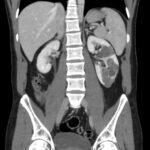

Email enquiry from GP: This 49 year old man had an abdominal CT as part of an emergency assessment for ?appendicitis. No explanation for the pain was found, but he was noted to have multiple simple cortical cysts in his … Continue reading